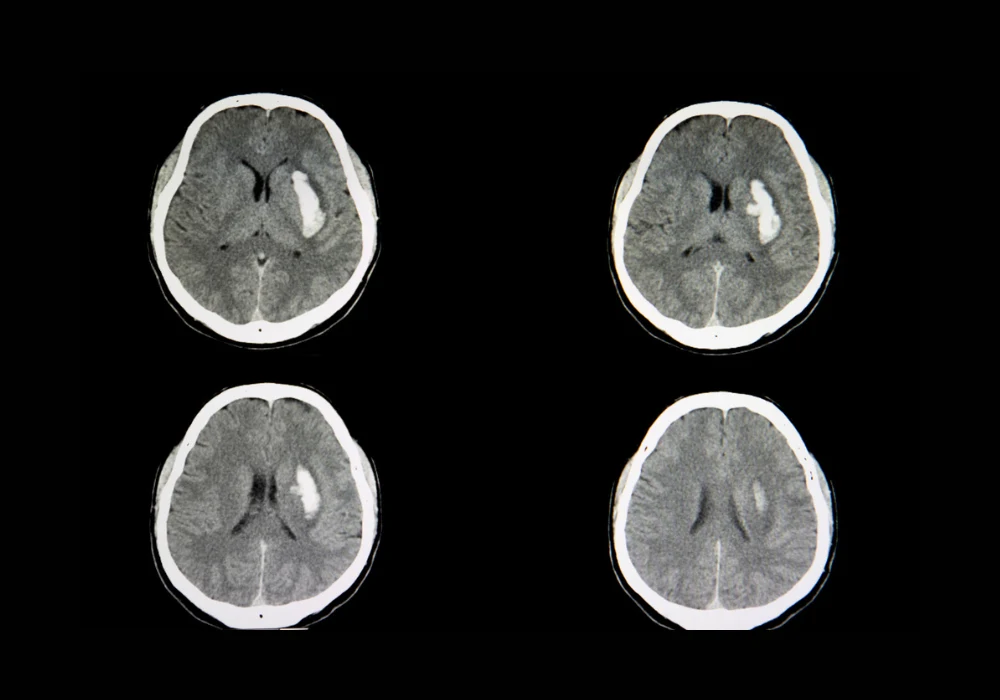

Artificial intelligence has become an integral part of radiology, particularly in high-demand settings such as emergency and teleradiology services. Non-contrast head CT scans are central to evaluating acute emergencies including intracranial haemorrhage, a condition with a 44% mortality rate within 30 days and a recovery rate of only 20% at six months. These figures underscore the urgency of rapid and accurate diagnosis. However, off-hour workloads raise the risk of diagnostic error, prompting growing reliance on AI-based detection systems to support radiologists. While such tools demonstrate high sensitivity and specificity, their performance is not fixed and may drift over time due to evolving clinical practices, demographic changes or equipment variability. Continuous monitoring therefore becomes essential. A recent evaluation of a commercial AI system for haemorrhage detection, supported by a large language model, highlights the potential of combining algorithmic performance with scalable monitoring strategies to improve clinical reliability.

The multi-centre evaluation analysed 332,809 head CT scans from 37 radiology practices across the United States between December 2023 and May 2024. Of these, 13,569 were flagged as positive for haemorrhage by the Aidoc AI system. To validate performance and establish ground truth, 200 randomly selected positive cases underwent review by experienced radiologists who were blinded to AI outputs. ChatGPT-4 Turbo, deployed on a HIPAA-compliant platform, was used to extract haemorrhage-related findings from the Impression sections of radiology reports. Prompt engineering was refined through testing on over 1,000 reports to ensure optimal accuracy in classification.

When assessed against radiologist-confirmed cases, ChatGPT achieved a positive predictive value of 1 and a negative predictive value of 0.988, with overall accuracy of 0.995 and an area under the curve of 0.996. Only one false negative was identified, caused by a report in which the relevant description appeared outside the Impression section. No false positives occurred. These results demonstrate that a large language model can reliably extract structured data from free-text reports without the need for extensive human annotation, significantly reducing the resources required for post-deployment monitoring. In this evaluation, ChatGPT achieved robust concordance with ground-truth data, highlighting its potential as a scalable tool for continuous oversight of deployed AI systems.

Aidoc demonstrated strong diagnostic accuracy but generated false positives influenced by several clinical and technical factors. Statistical analysis showed that scanner manufacturer played a critical role. Philips scanners were associated with a significantly higher false positive rate than GE Medical Systems, with an odds ratio of 6.97 in multivariate analysis. Imaging artefacts also contributed, with an odds ratio of 3.79, while the presence of neurological symptoms increased false positives with an odds ratio of 2.64. In contrast, midline shift and mass effect reduced the likelihood of false positives, suggesting that larger or more evident haemorrhages enhanced detection reliability.

Radiologists using Aidoc achieved a sensitivity of 0.936 and specificity of 1, with accuracy of 0.96 and an area under the curve of 0.98. However, discrepancies were noted. Seven haemorrhages were missed by radiologists but correctly identified by the AI system, most of them during night shifts in emergency rooms. This reflects the impact of workload on diagnostic accuracy and highlights where AI assistance can reduce error. At the same time, the system produced 71 false positives that radiologists identified as negative, and one case demonstrated automation bias when a radiologist deferred to an incorrect AI-positive classification. These findings indicate both the potential benefits and the safety concerns of integrating AI into clinical workflows.